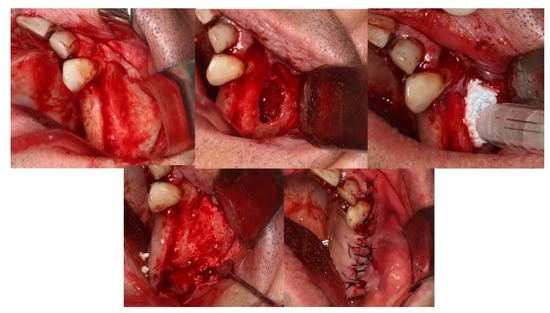

4.3. Patient No. 3

| 3 M 61 | NO [-] Alveolar ridge preservation | Yes [No] | G | No | G | No | No osseointegration of the implant, replacement in 3 months, without problems and with good stability |